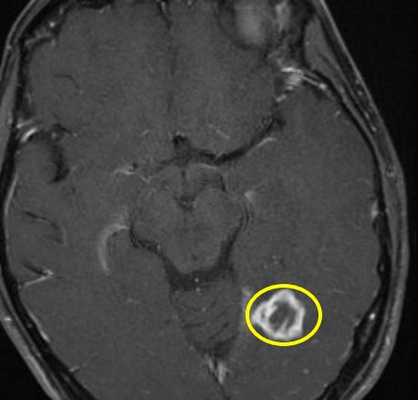

Туберкулемы имеют вид “мишеней” с кальцификацией в центре. При МРТ с контрастированием хорошо усиливаются по периферии.

МРТ головного мозга с контрастированием. Туберкулема.